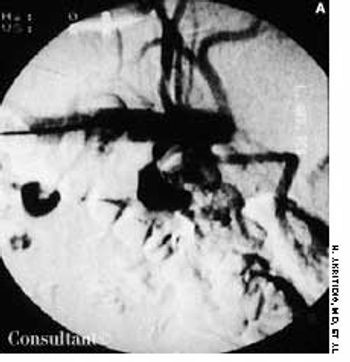

Police brought a delirious, combative 24-year-old man to the emergency department. The patient was unable to provide any history on arrival, but his scarred, blistering lips and his vital signs (blood pressure, 166/102 mm Hg; heart rate, 97 beats per minute; respiratory rate, 24 breaths per minute; and temperature, 38.2°C, or 100.9°F) led to a possible diagnosis of cocaine-induced delirium.